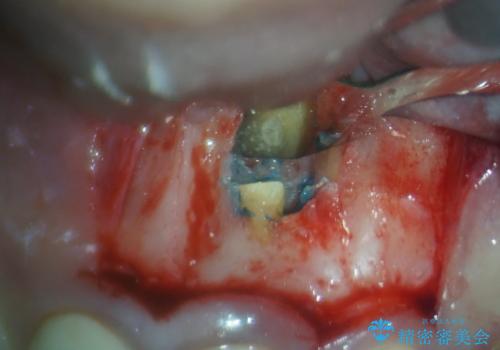

治療の選択肢としては、①セラミッククラウンを壊して再度根管治療を行い、その後セラミッククラウンを製作する、②当該歯の歯根端切除術を行う、のいずれかとなります。

歯根端切除術では、術後に歯肉ラインが偏位し、セラミッククラウンと歯の境目が目立つことがありますが、患者様と相談の上、②歯根端切除術にて治療を行うこととしました。